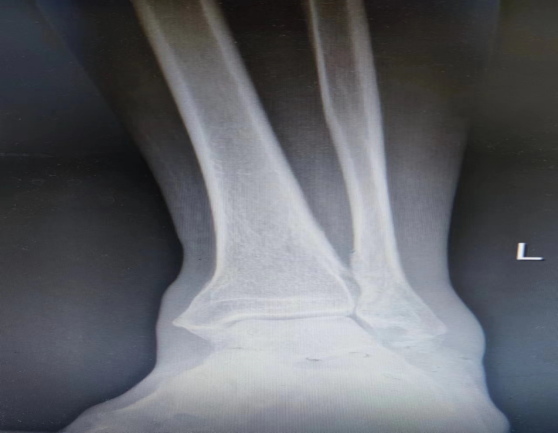

放血疗法操作方便,效果更好,见效更快。患者,52岁的刘女士,2天前跑步时不慎扭伤左踝,致左踝关节肿胀、疼痛、活动受限,至当地医院行X线,未见明显骨折,诊断为外左踝关节扭伤,给予冰敷及外用药物贴敷等治疗,症状未见明显缓解,遂至云南省中医医院就诊。查体:左踝关节明显肿胀,皮肤淤青,压痛明显,活动受限,背伸5°,跖屈15°,肢端感觉及血运良好。辅助检查:X线示:左踝关节未见明显骨折,软组织肿胀。中医诊断:筋痹-瘀血阻滞;西医诊断:左踝关节扭伤。